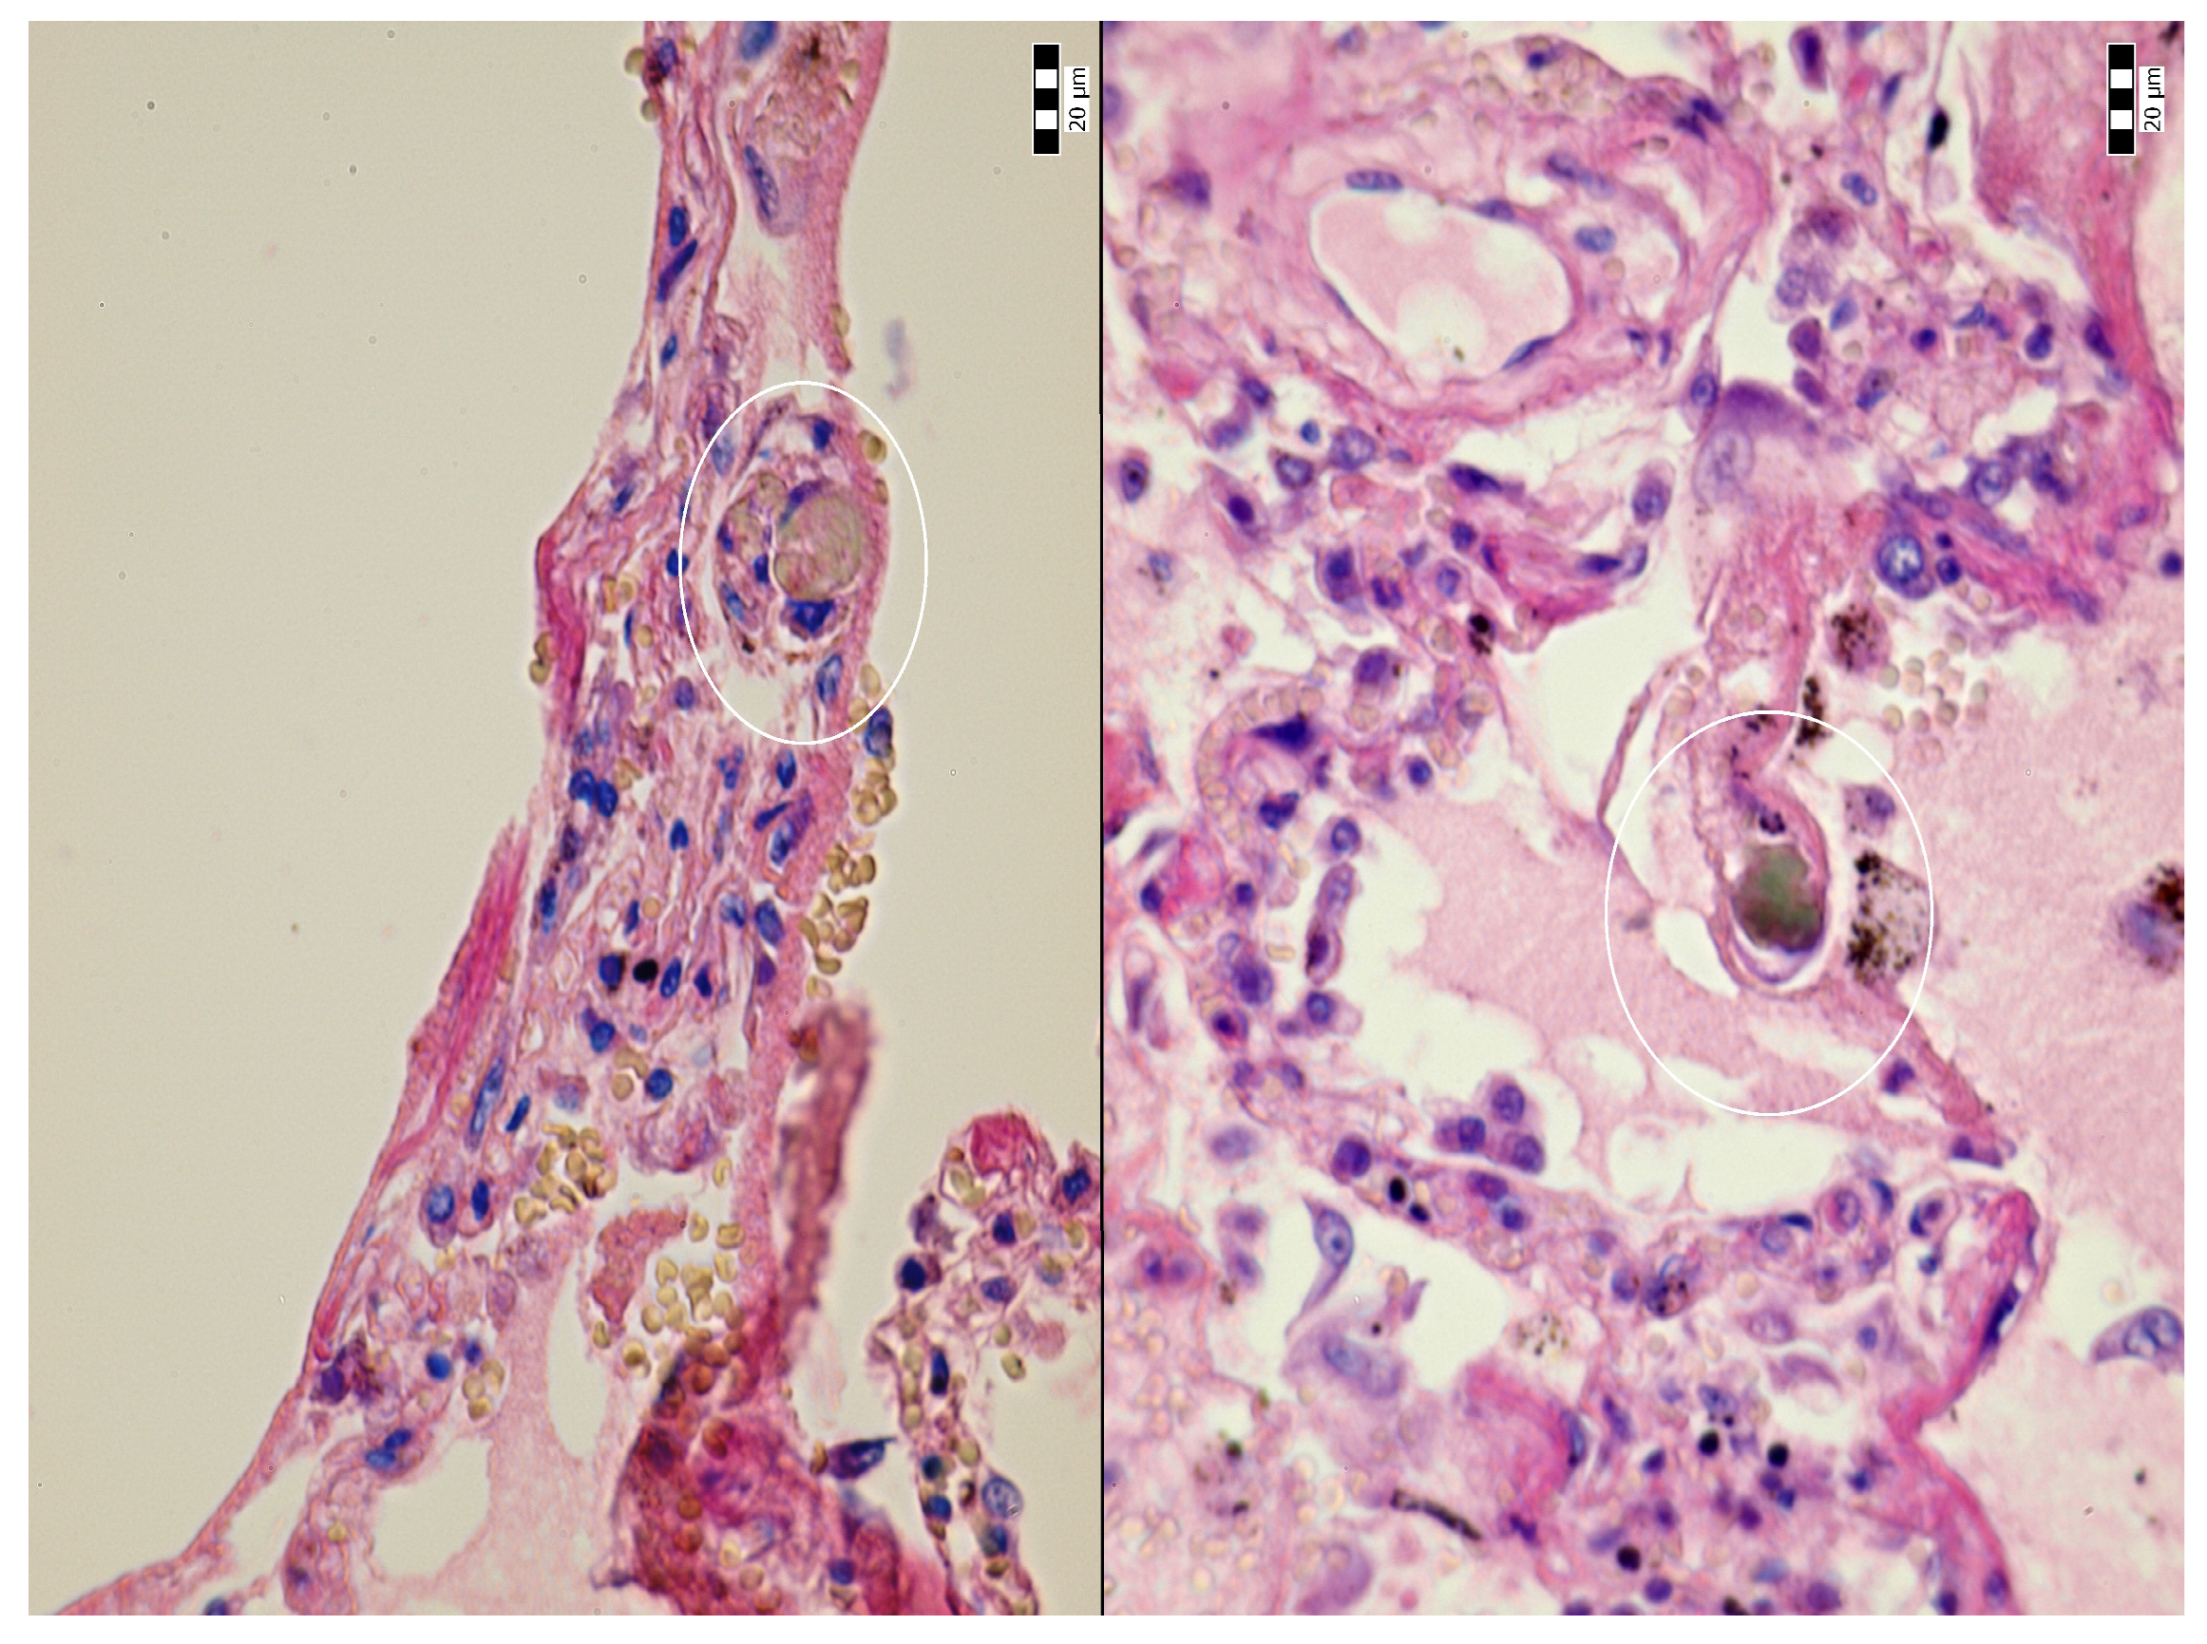

Alveolar Bile and Light Chain Immunoglobulin Depositions as an Unusual Complication of Transjugular Liver Biopsy Resulting in Bilhemia in a Patient with Multiple Myeloma

2. Case Description